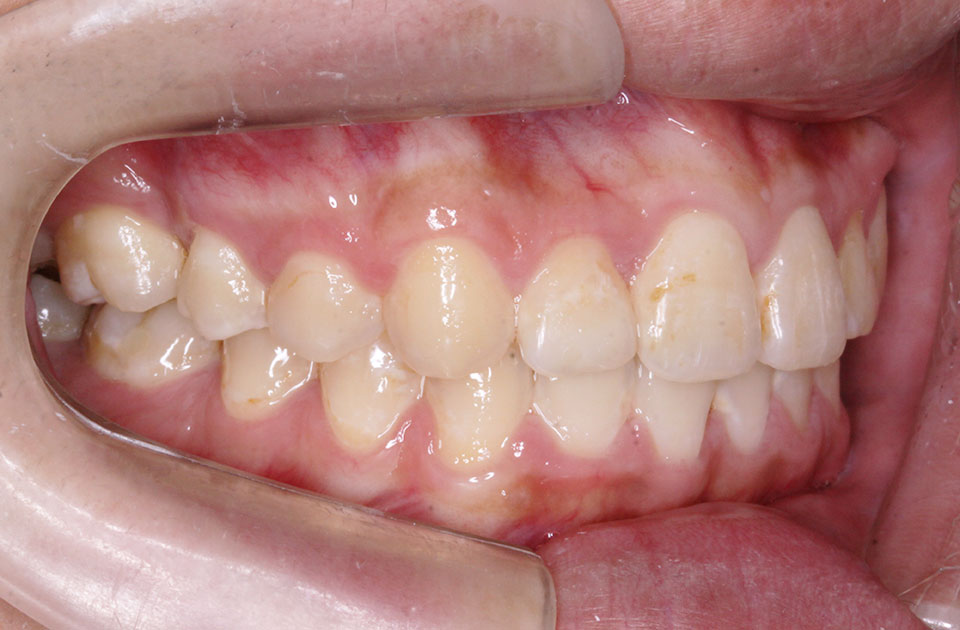

矯正前

矯正前 右側

矯正前 左側